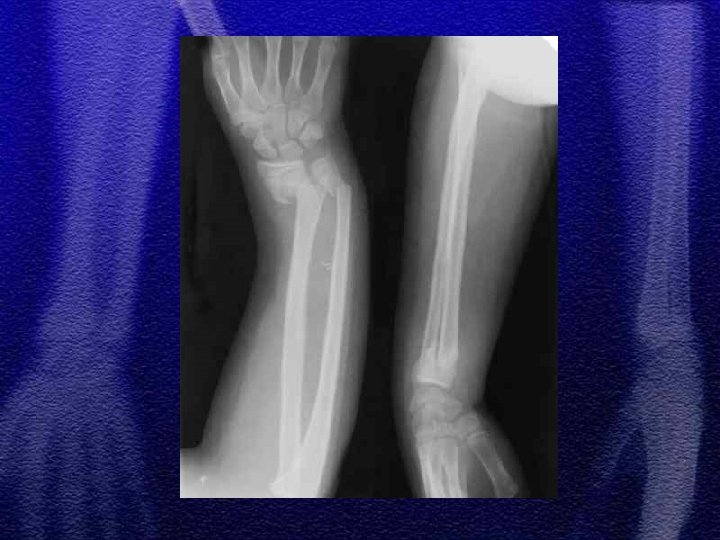

§ Specyficzne - to złamanie typu „zielonej gałązki”, przy złamaniach tego typu okostna nie jest uszkodzona całkowicie, dotyczy to również warstwy korowej § Przy repozycji należy złamać pozostałą warstwę korową, ponieważ zapobiega to wtórnemu przemieszczeniu

§ U dzieci starszych podobnie jak u dorosłych przydatny jest podział dotyczący lokalizacji złamania - określający 3 strefy złamania § W wieku rozwojowym rzadko występuje złamanie typu Galeazzi odmiana dziecięca to złamanie dalszej przynasady kości promieniowej ze złuszczeniem dalszej nasady kości łokciowej

§ Najczęściej repozycja zamknięta § Konieczne kontrole rtg. w 3, 7, 14 dobie z uwagi na możliwość wtórnego przemieszczenia § Leczenie operacyjne - płytki, drut Kirschnera

§ Wyznaczenie jednoznacznego kryterium do zaakceptowania zrostu nieprawidłowego we wstępnej fazie leczenia jest trudne § Przemieszczenie do boku nawet o szerokość trzonu można zaakceptować § Przemieszczenia kątowego >20° nie można akceptować § Przemieszczenia rotacyjne nie podlegają korekcji § Zasadnicze znaczenie ma wiek dziecka

§ Złamania przynasad § Złuszczenia dalszej nasady kości promieniowej to najczęstszy uraz chrząstki nasadowej u dzieci § Najczęstsze złuszczenia typ I i II § Typ III IV i V występują sporadycznie, są obarczone możliwością wywołania zaburzeń wzrostu kości (zniekształcenia pseudo-Madelunga)